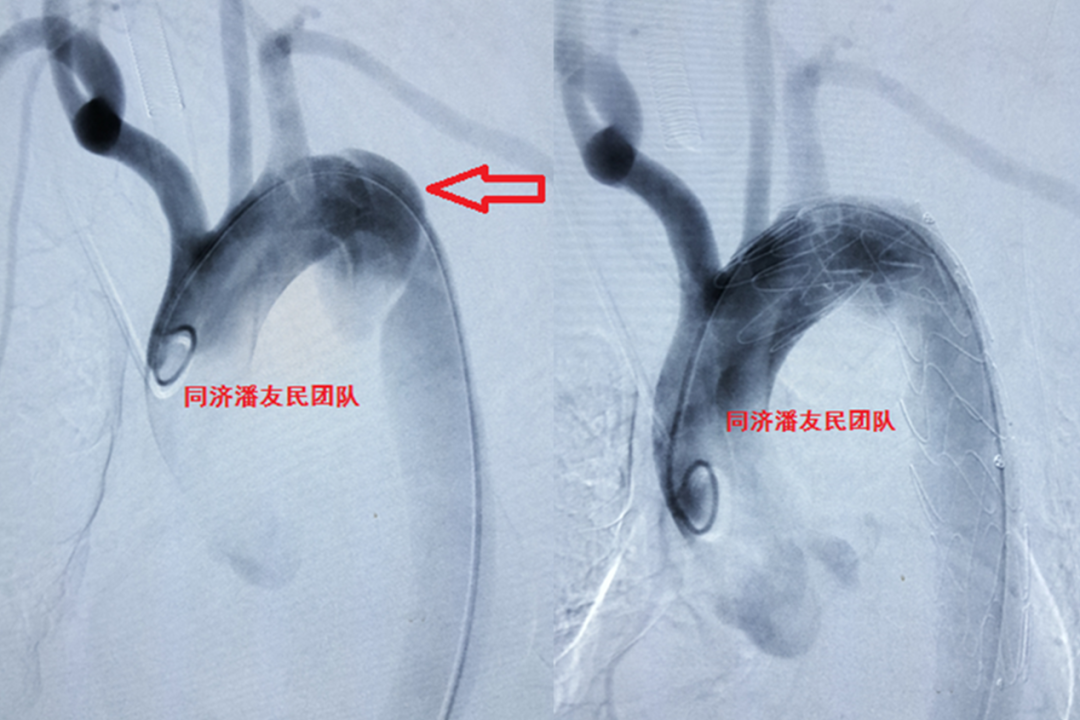

除了局限性主动脉夹层外,也可以表现为非局限性夹层,即普通类型的降主动脉夹层(图6)。

图6 左图为局限性外伤性主动脉夹层(白箭头所示)。右图为非局限性外伤性主动脉夹层。